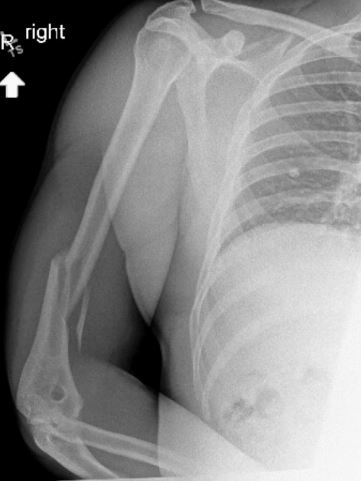

환자의 오른쪽 팔 윗부분에 변형이 관찰됐고 상완골 바깥쪽으로 심한 압통이 확인됐다. 환자는 통증으로 인해 팔을 스스로 움직일 수 없는 상태였다. 이어진 엑스레이 검사 결과, 상완골 중간 부위에 나선형 골절이 확인됐다.